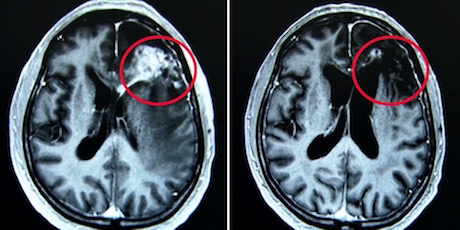

Mittlerweile hat Claudia Friesen mehr als 350 Patientendaten gesammelt, die allesamt positive Krankheitsverläufe zeigen. Auf den MRT-Bildern ist zu sehen, dass sich Metastasen zurückbildeten, wenn die Betroffenen die Chemotherapie mit Methadon ergänzten. Selbst grosse Tumore im Hirn, die auf keine Therapie mehr ansprachen, verschwanden (Bild unten).

Hirntumor wurde mit Krebspillen+Methadon geheilt

Ein Beispiel ist Sabine Kloske. Vor mehr als zwei Jahren wurde bei ihr ein Glioblastom diagnostiziert. Dieser schnell wachsende, bösartige Hirntumor gilt derzeit als unheilbar. Die Ärzte sagten der damals 36-Jährigen, sie habe nur noch etwa 15 Monate zu leben. Doch es kam anders: Seit mehr als zwei Jahren ist der Tumor nicht zurückgekehrt. Sabine Kloske führt dieses Wunder auf das Methadon zurück. Zusätzlich zur Chemotherapie nimmt sie zweimal täglich 35 Tropfen davon und ist wieder voller Zuversicht: «Ich bin wieder da. Kann weiterleben und muss nicht sterben.»